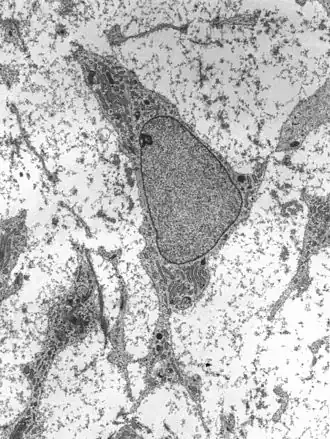

Transmission electron micrograph of a mesenchymal stem cell displaying typical ultrastructural characteristics | |

Mesenchymal stem cells (MSC) or mesenchymal stromal cells, also known as medicinal signaling cells are known to be multipotent, which can be found in adult tissues, for example, in the muscle, liver, bone marrow and adipose tissue. Mesenchymal stem cells usually function as structural support in various organs as mentioned above, and control the movement of substances. MSC can differentiate into numerous cell categories as an illustration of adipocytes, osteocytes, and chondrocytes, derived by the mesodermal layer.[34] Where the mesoderm layer provides an increase to the body's skeletal elements, such as relating to the cartilage or bone. The term "meso" means middle, infusion originated from the Greek, signifying that mesenchymal cells are able to range and travel in early embryonic growth among the ectodermal and endodermal layers. This mechanism helps with space-filling thus, key for repairing wounds in adult organisms that have to do with mesenchymal cells in the dermis (skin), bone, or muscle.[35]

Mesenchymal stem cells are known to be essential for regenerative medicine. They are broadly studied in clinical trials. Since they are easily isolated and obtain high yield, high plasticity, which makes able to facilitate inflammation and encourage cell growth, cell differentiation, and restoring tissue derived from immunomodulation and immunosuppression. MSC comes from the bone marrow, which requires an aggressive procedure when it comes to isolating the quantity and quality of the isolated cell, and it varies by how old the donor. When comparing the rates of MSC in the bone marrow aspirates and bone marrow stroma, the aspirates tend to have lower rates of MSC than the stroma. MSC are known to be heterogeneous, and they express a high level of pluripotent markers when compared to other types of stem cells, such as embryonic stem cells.[34] MSCs injection leads to wound healing primarily through stimulation of angiogenesis.[36]